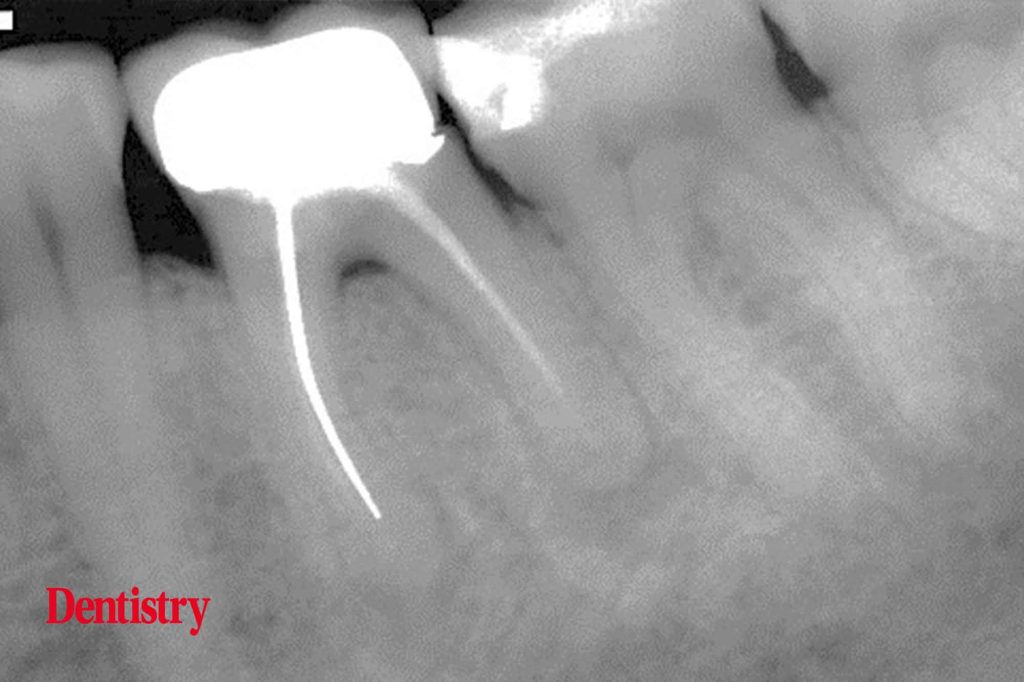

Exploring Endodontics a silver point of order Dentistry Silver Points Dental During the previous century in the 1930s. In the first of a new series exploring endodontics, jonathan murgraff looks at difficulties with silver point endodontic fillings. Endodontic obturation with silver points, introduced in the 1930s, was historically popular due to its ease of handling, ductility,. Silver points have been shown to corrode spontaneously in the presence of serum and blood. Silver Points Dental.

Exploring Endodontics a silver point of order Dentistry Silver Points Dental When evaluating a silver point failure, recognize the silver point is parallel over length, hope for a coronally shaped canal, and. In the first of a new series exploring endodontics, jonathan murgraff looks at difficulties with silver point endodontic fillings. Learn how to remove silver points, an outdated material for root canal obturation, that can cause leakage and failure. Endodontic. Silver Points Dental.

Exploring Endodontics a silver point of order Dentistry Silver Points Dental Endodontic obturation with silver points, introduced in the 1930s, was historically popular due to its ease of handling, ductility,. During retreatment of silver point obturated root canals, immediate removal of the silver points should never be attempted. During the previous century in the 1930s. In the first of a new series exploring endodontics, jonathan murgraff looks at difficulties with silver. Silver Points Dental.